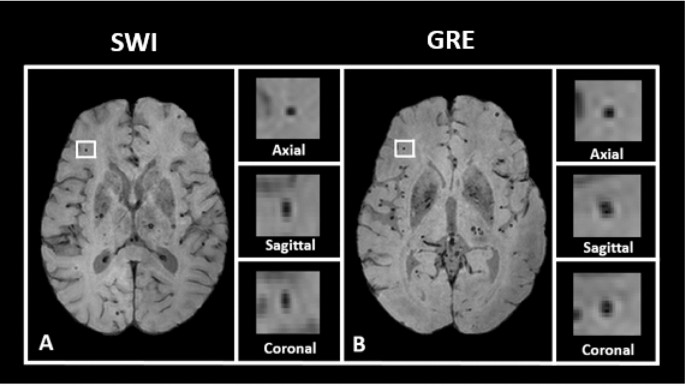

Microbleeds are detected radiologically with T2*-weighted MRI images, including either gradient echo (GRE) or susceptibility weighted images (SWI)1,2,3,4,5,8,9,10. These radiological findings have been validated with post-mortem analysis6,7, with true positives captured on imaging 48–89% of the time, depending on acquisition parameters5. Given the high level of sensitivity of MRI to paramagnetic material and the small size of the deposits, it is possible that MRI is more sensitive than gross pathological examination4,10,11,23. By omitting a refocusing pulse used in spin-echo sequences (such as T1) to correct of susceptibility distortion, GRE MRI is sensitive to paramagnetic artifacts, which can be exploited to visualize cerebral microbleeds5,24. SWI MRI is an alternative, more sensitive imaging modality for microbleed detection, with a larger “blooming” effect of paramagnetic material, making microbleeds more easily visible but also potentially more irregularly shaped23,24. Figure 1 shows an illustration of a microbleed using both SWI and GRE, highlighting the differences between the two modalities.

Examples of microbleed location. The participant’s MRI shown here reflects a heavy burden of cerebrovascular disease. (A) Left: axial slice of a SWI image, with a microbleed location highlighted in white. Right: an enlarged image of the highlighted location. From top to bottom, the views shown are axial, sagittal, and coronal. (B) Left: axial slice of the same participant’s GRE image, with the same microbleed location highlighted in white. Right: an enlarged image of the highlighted location. From top to bottom, the views shown are axial, sagittal, and coronal.